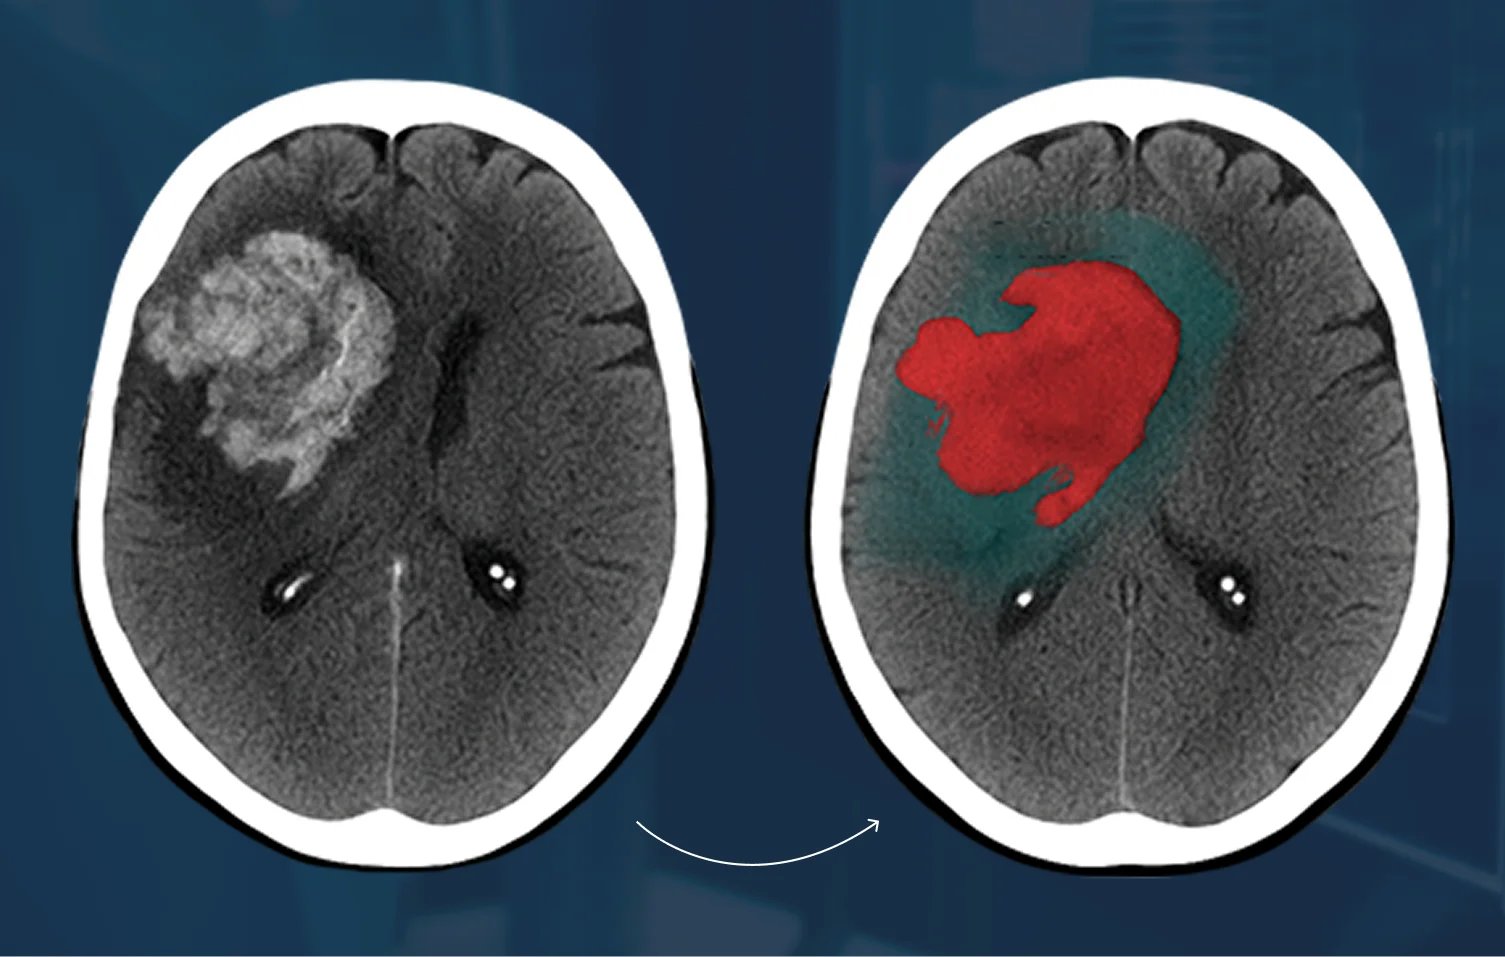

• Precise Lesion Segmentation

• Disease Pathology Segmentation

Precise segmentation is essential for training medical AI models that require detailed anatomical or pathology-level understanding. High-accuracy masks enable models to measure volumes, isolate target regions, track disease progression, and differentiate tissue types with clinical reliability. Inaccurate segmentation introduces noise into the training dataset, resulting in unstable models, poor generalization, and reduced diagnostic value. High-fidelity segmentation ensures your AI performs consistently, safely, and at a standard suitable for clinical applications.